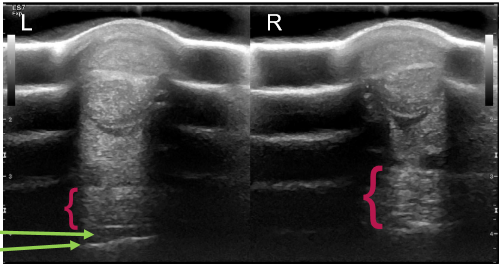

• does this show a manica flexoria tear or is it normal?

normal

tear